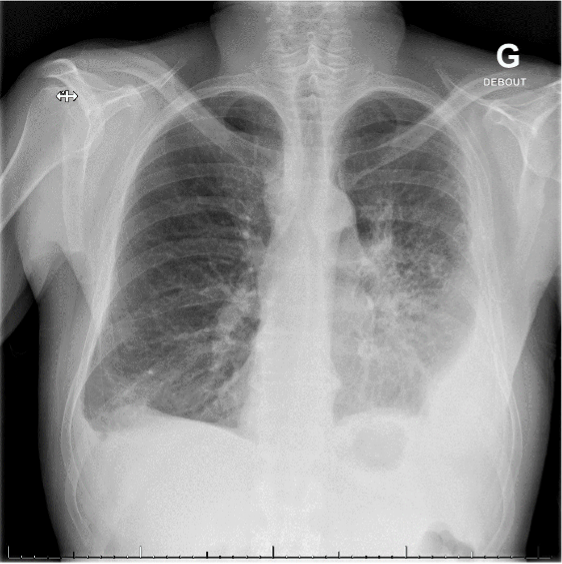

Au laboratoire, on retrouve le plus souvent une augmentation des paramètres inflammatoires et des troponines. Selon l’étiologie, d’autres valeurs peuvent être perturbées. Les modifications typiques de l’ECG sont une surélévation diffuse du segment ST et un PR descendant. La radiographie du thorax peut montrer un élargissement de la silhouette cardiaque faisant suspecter un épanchement, ou aider dans la recherche de l'étiologie. L’échocardiographie permet de rechercher un épanchement péricardique et de visualiser les répercussions au niveau de la fonction cardiaque. En cas de douleur thoracique rétrosternale, la priorité est d'exclure une coronaropathie par coro-scanner ou coronarographie.

Image proposée par l'Hôpital Riviera-Chablais.